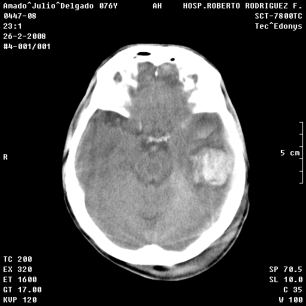

An example of an applications of our proposed strategy to a medical image is shown in Figure 7. In this case, we used different values of and in the . This is a preliminary result. A deeper paper about these results will be published.